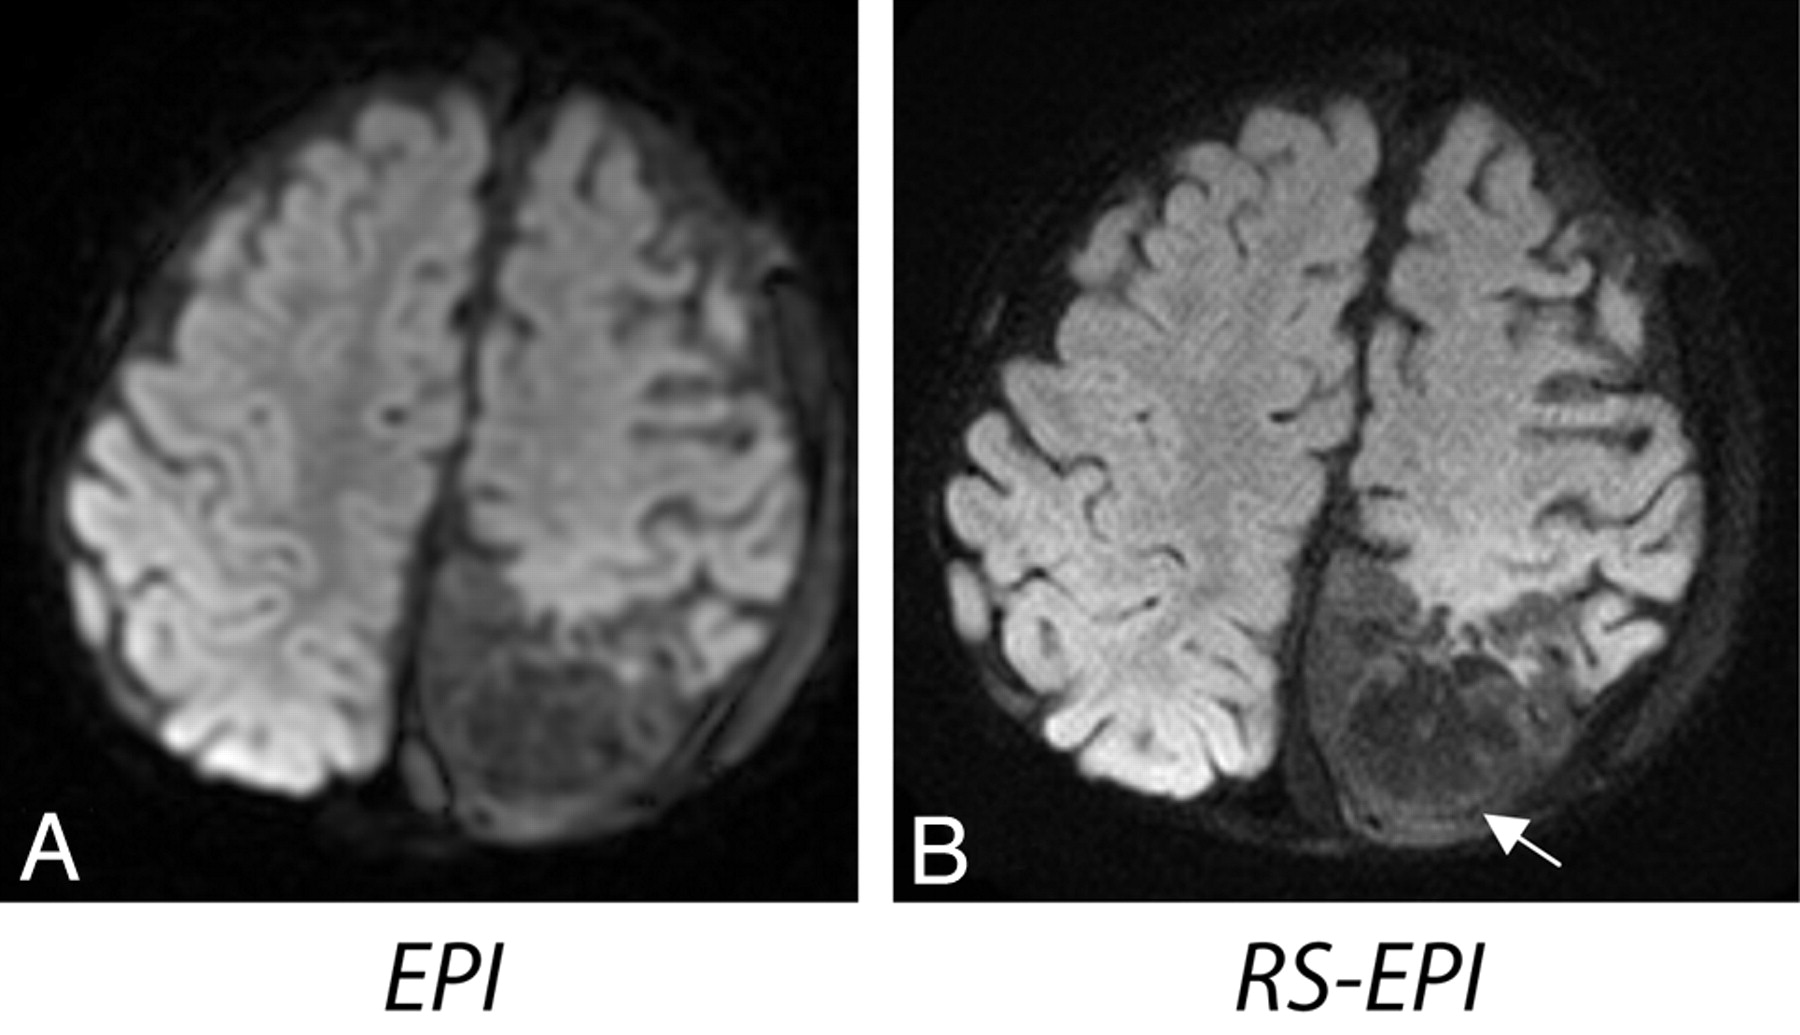

The average scores calculated across 35 patients are shown in Fig 2. The following scores were given to EPI, RS-EPI, and RS-EPI re-evaluated alongside the EPI, respectively: resolution, 3.5/5.8/5.2; distortion level, 2.9/5.5/6.0; SNR, 3.4/4.2/4.1; lesion conspicuity, 3.3/6.0/5.9; and diagnostic confidence, 3.2/5.8/6.0. The P values for EPI versus RS-EPI viewed first independently and then as a direct comparison, were as follows: resolution, 1.9 × 10−6/1.2 × 10−6; distortion level, 1.3 × 10−6/9.5 × 10−7; SNR, .006/.007; lesion conspicuity, .005/.007; and diagnostic confidence, 1.3 × 10−6/1.9 × 10−6. Overall, the RS-EPI had significantly improved diagnostic confidence. RS-EPI identified a lesion not found by EPI in 1 patient (a small subdural empyema, Fig 3) and more accurately defined the extent and location of the lesions, such as ischemic injury, metabolic disorder (Fig 4), a cystic encephalomalacia (Fig 5), and a skull base tumor. In 1 case, RS-EPI (Fig 6B) correctly identified a false-positive ischemic lesion in the temporal lobe seen on EPI in a patient with Moyamoya disease (Fig 6A). In another case, RS-EPI (Fig 6D) correctly identified a false-negative ischemic lesion in the temporal lobe in a postoperative patient with Moyamoya disease, where this was presumed to be a post-operative blood-product artifact on EPI. (Fig 6C).

Two patients with Moyamoya disease. A and B, An 8-year-old girl presenting with possible infarct or blood product at the surgical site on EPI (solid white arrow). The absence of these distortion artifacts on RS-EPI makes this confidently negative. The open white arrows indicate undesirable brightening of the flocculus due to susceptibility artifacts from the brain/bone interface. C and D, A 3-year-old boy presenting with possible postoperative blood-product artifacts on EPI (white arrow), but the lesion appears more suspicious for an ischemic lesion on RS-EPI. On closer inspection, the lesion demonstrates subtle cortical T2 high intensity on the T2 FSE sequence, confirming the suspicion that this represents a true ischemic focus, rather than distortion related to postoperative changes. These 2 cases demonstrate that RS-EPI is both sensitive and specific.